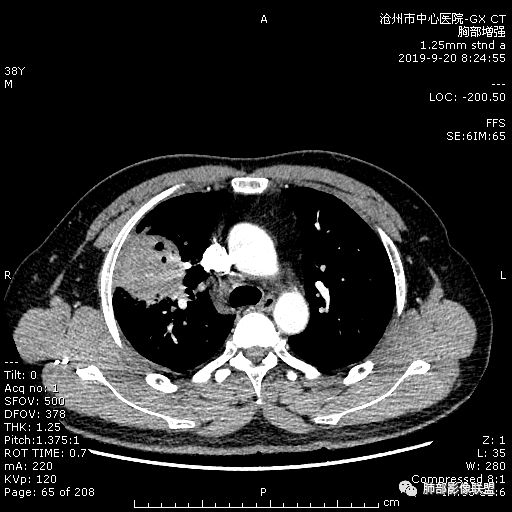

年轻男性,咳嗽2月,痰中带血,胸痛,炎症指标稍高,肿标正常。影像,右肺上叶不规则团块影,浅分叶,伴边界不清磨玻璃影,从外周向内分布,局部胸膜增厚,病灶中央坏死,坏死边界尚清,空洞形成,空洞内壁光滑;考虑炎性肉芽肿性病变,结核可能,鉴别恶性肿瘤及真菌感染。病灶分布特点不考虑隐球。

38岁,男性,慢性咳嗽2月,右胸痛8天,无发热;白细胞高,肿瘤标志物不高;右上肺不规则块状影,周围有磨玻璃影,边界清,整体有膨胀感,分叶,与胸膜糊墙,并见栽赃,增强肿块中央坏死,周边强化。综合考虑,考虑恶性,鳞癌可能。

38岁,男性,慢性咳嗽2月,右胸痛8天,无发热。白细胞高,肿瘤标志物不高。右上肺不规则块状影,周围有磨玻璃影,边界模糊,整体有膨胀感,分叶,与胸膜糊墙,可疑栽赃,增强肿块中央坏死,边界清,周边强化明显,强化区有低密度影,壁不规则,跨叶生长,支气管截断,伴支气管扩张,综合考虑腺癌

晨读:右肺上叶不规则团块,深分叶,膨胀为主,有部分收缩,叶间裂牵拉上移,内多液化坏死,有支气管扩张,右肺上叶大支气管近端通畅,远端堵塞,说明肿块来源于外周,纵隔及右肺门淋巴结肿大,胸膜糊墙为主,年轻人,肿标不高,炎性指标高,综合考虑炎性肉芽肿放前面脓肿,结核,肿瘤放后面。

中年男性,咳嗽2月病史伴胸疼。白细胞及中性粒细胞高。右上肺团块影,边缘平直内收,与胸膜宽基底相连,胸膜肥厚,肿块内多灶性坏死,有空泡征,支气管进入,走行自然,近端有阻塞,考虑感染性疾病,肺脓肿。但是有深分叶,鳞癌合并感染也不排除。

3.ct表现:肺脓肿可呈结节状或团块状,有时呈不规则形,气道来源肺脓肿常单发,血行来源常多发,边缘模糊,部分病灶周围可见片状肺实变及磨玻璃影;病灶中央为液化坏死区,若脓肿与支气管相通,脓液排出可形成空洞,空洞内可形成液平;急性肺脓肿内壁多不规则;慢性肺脓肿洞壁较厚,一般不规则或形成多房空洞:CT增强扫描空洞壁可见强化,空洞壁为纤维肉芽组织,呈典型的环形强化;慢性肺脓肿周围可有较广泛的纤维索条影,可伴支气管扩张.肺

气肿或胸膜增厚表现。

今天病例坏死周围也可以看到明显强化的脓肿壁,只是局部脓肿壁不规则模糊,部分脓肿壁规则清楚。